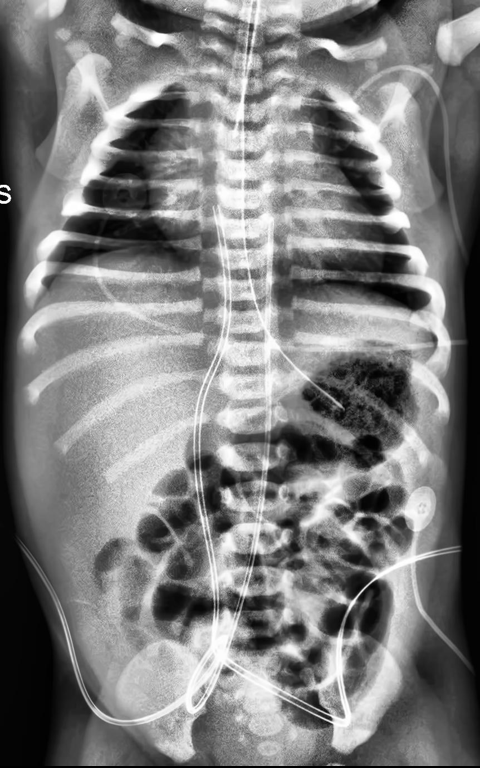

Automated catheter detection is a challenging task. Although most catheters have a radiopaque strip to facilitate detection, the strip may become less apparent depending on the projection angle. Catheters maybe confused by other similar linear structures like ECG leads and anatomy including ribs. Additionally, portions of catheters can be occluded by anatomical structures given that radiographs are a 2D projection of a 3D structure. For example, when a NGT is placed within the oesophagus, the catheter itself becomes less apparent due to the high density of the adjacent vertebrae. Finally, the number and type of catheters that could possibly appear in pediatric X-rays are unknown a priori. The catheters may be intertwined with each other thus making simple line tracing methods fail. Figure 1 gives three sample pediatric X-ray images with some common catheters highlighted in different colors.

To alleviate this annotation problem in catheter detection, we proposed to use X-ray images with simulated catheters by exploiting the fact that catheters are essentially tubular objects with various cross sectional profiles. To be more specific, a synthetic 2D projection of a catheter is generated by first simulating a horizontal catheter profile and then using it as a brush tip to draw along a B-spline path. This generated catheter is then composited with an X-ray image serving as the training data. Another contribution of this work is a segmentation network that can inherently take into account multi-scale information. This network adopts a UNet-style form and contains a recurrent module that can process inputs with increasing scales111Our code is available at https://github.com/xinario/catheter_detection.git.. We have empirically shown that by iterating through the scale space of the input image, higher recall is achieved as compared to using a single scale. Details about the methods are discussed in Section 3. Three sample detection results are shown in Figure 1.

The test dataset is collected locally and only contains frontal chest-abdominal X-rays from patients < 4 weeks old. This is the most common radiograph obtained to confirm placement of catheters such as UACs and UVCs in neonates. Currently, the test set has 35 fully labeled images with different catheter types with sample images previously shown in Figure 1. All the annotated catheters (lines excluding ECG leads) are treated as the same class in the detection.